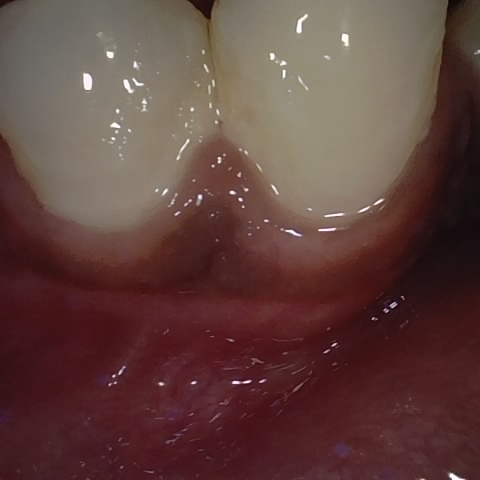

Annotated as "Good"